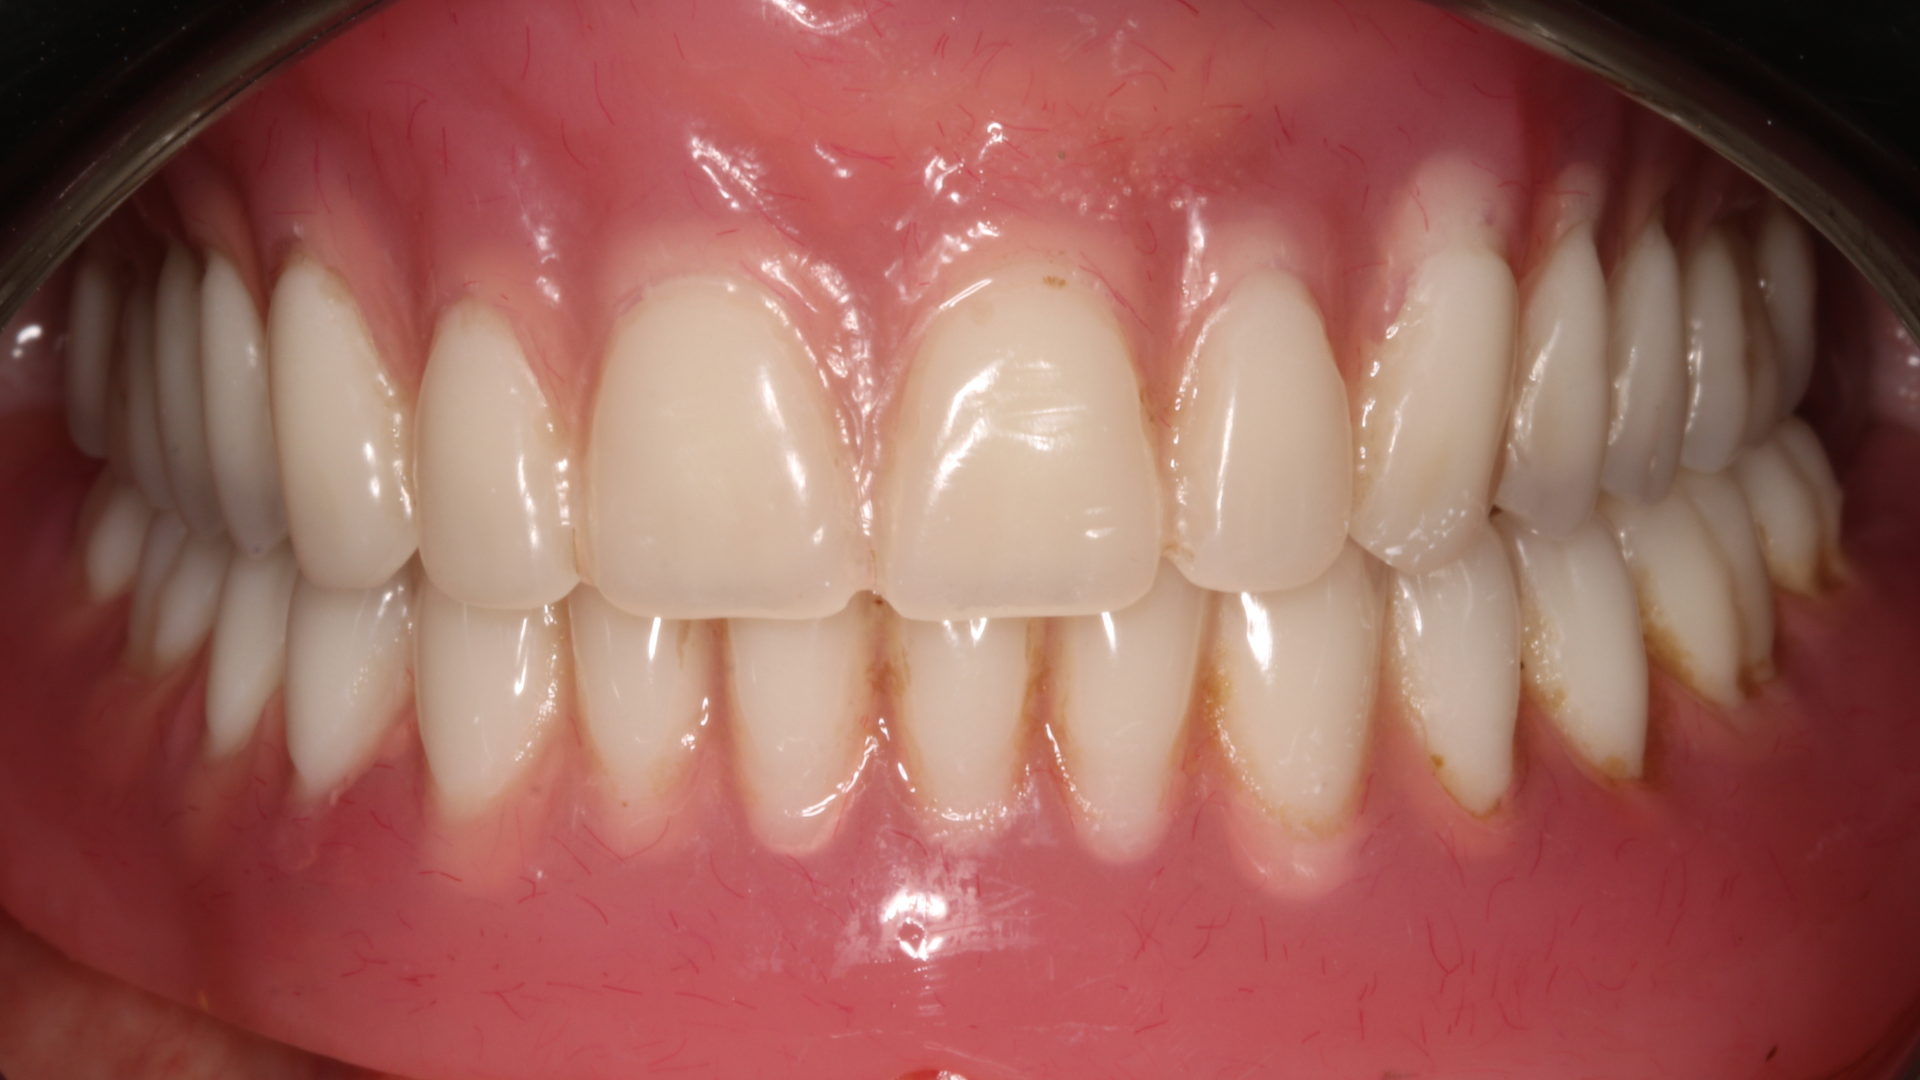

Réhabilitation complète bi maxillaire